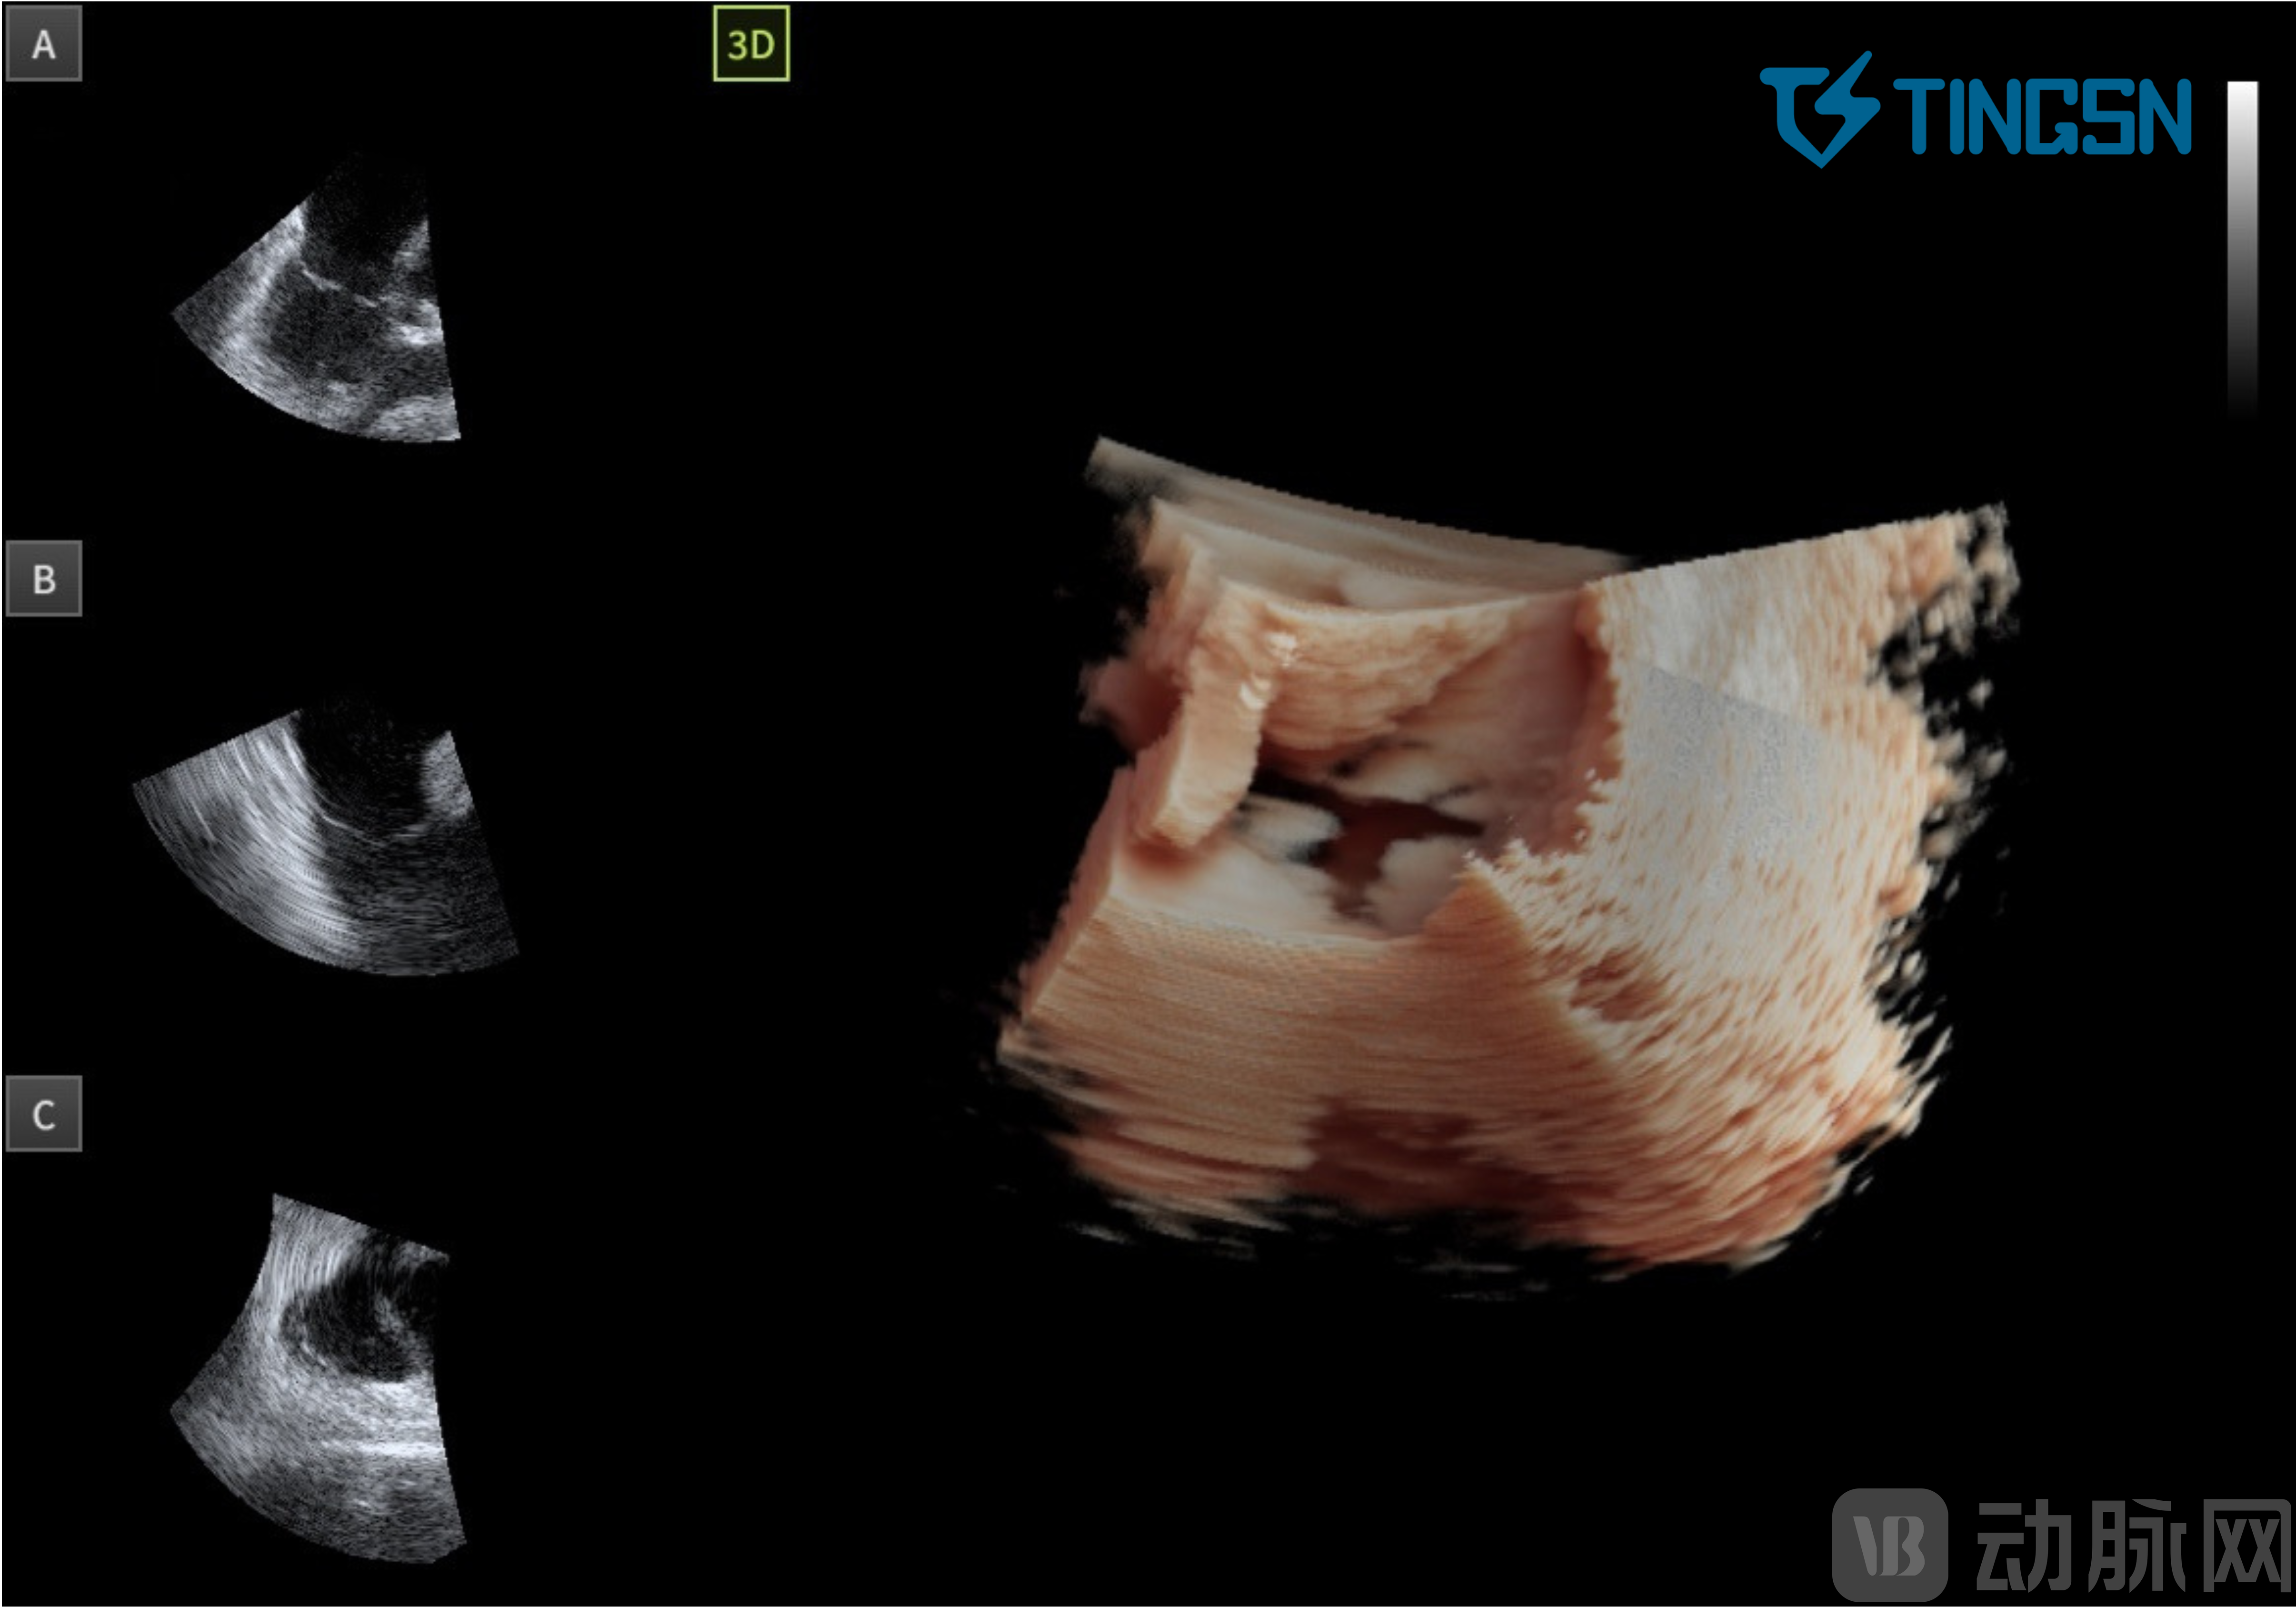

01 心室收缩期 三尖瓣瓣叶呈闭合状态

02 心室舒张期 三尖瓣瓣叶呈开放状态